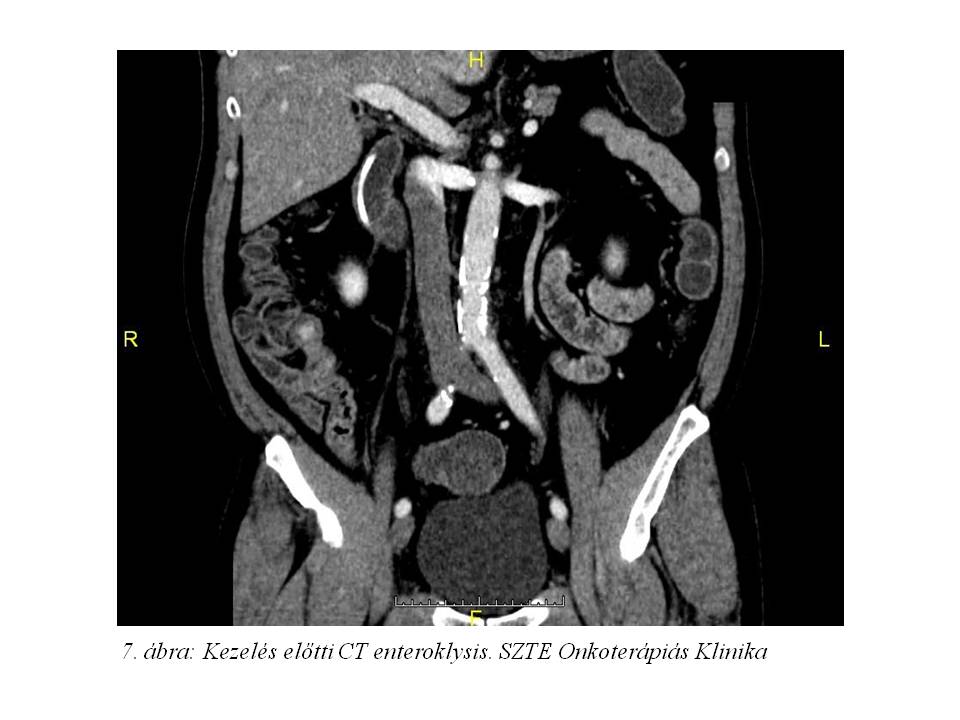

Tekintettel a diagnózis óta eltelt több hónapra re-staging hasi MR (4. ábra) és CT enteroklysis vizsgálat (5. ábra, 6. ábra, 7. ábra) történt. Az előbbi változatlan állapotot írt le, azonban az utóbbin a terminális ileum kezdeti szakaszán kb. 1,1x1,8x10 mm-es térszűkítő folyamat is ábrázolódott, mely megfelel a primer neuroendokrin tumornak.